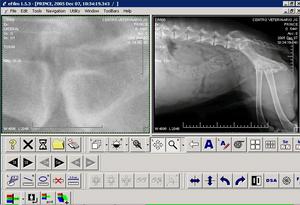

IMAGEN DICOM OBTENIDA. Se puede aumentar la calidad de la imagen variando el contraste o la iluminación |

MANEJO INFORMÁTICO DE LA IMAGEN. La imagen DICOM se exporta a un servidor DICOM que tiene software específico para este formato. |

SOFTWARE: manejo de las imágenes procesándolas de múltiples formas. |

DICOM. La imagen DICOM se puede examinar de múltiples formas: ampliando, en copia negativa, realzando , etc.. Sólo se puede manejar con software DICOM. |